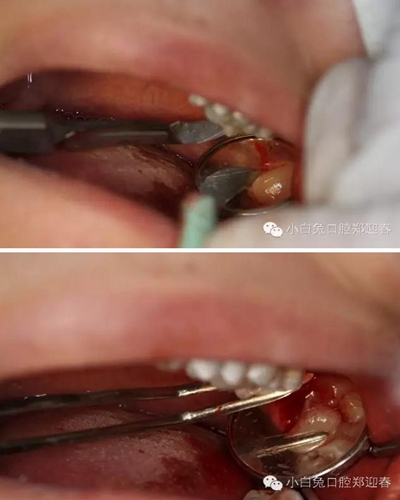

順著牙長軸的方向挺出牙根,這樣可以避免因為牙根旋轉(zhuǎn)對神經(jīng)管的影響。

處理牙槽窩,保留完整的牙槽骨形態(tài)。

置入膠原蛋白,縫合創(chuàng)口。

同期準備拔除28,28頰側(cè)牙尖萌出,余牙面均被牙齦覆蓋。

首先,必蘭0.5ml行上牙槽神經(jīng)和腭前神經(jīng)阻滯麻醉。

采用創(chuàng)面不縫合的切瓣方式

充分暴露牙冠部分

微創(chuàng)牙挺挺出28

創(chuàng)口置入膠原蛋白明膠

拔除術(shù)的離體28、38